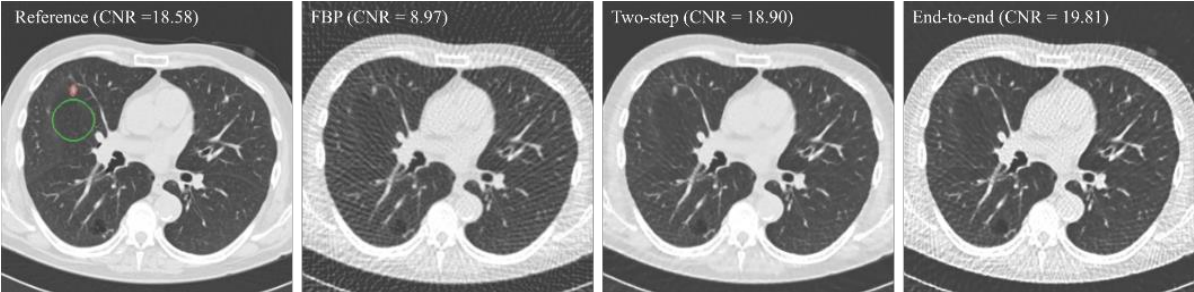

4.2 Reconstructed Images

end-to-end 방식은 줄무늬 구조가 보이는 반면 two-step 결과가 시각적으로 더 좋은 결과를 보여주었습니다.

하지만 Contrast to Noise Ratio(CNR)와 detection 성능에 대해서는 end-to-end 방식의 결과가 더 좋았습니다.

저자는 이런 결과를 바탕으로 사람과 달리 Computer Vision에서는 streak artifact 보다 CNR이 높을수록 better detection performance가 나온다고 생각하는 것 같습니다.

(human observer에게는 Computer Vision에서보다 streak artifact가 더욱 민감합니다.)

* FBP쪽을 보시면 streak artifact(줄무늬 구조)가 심하게 나타납니다.